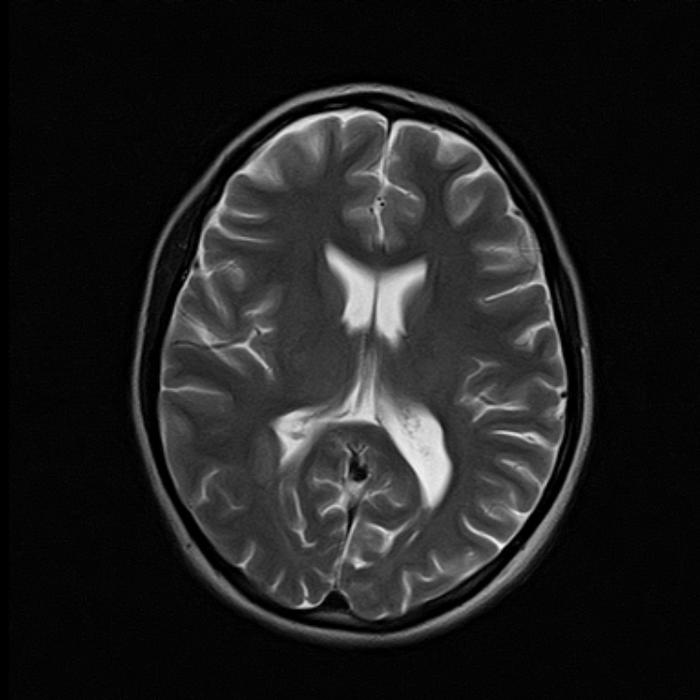

По итогам исследования, на снимках суб- и супратенториальных областей мозга выявлены единичные (в количестве трех) перивентрикулярные очаги: справа на уровне задних рогов боковых желудочков размером до 6х3 мм, слева до 5х3 мм и сверху правого бокового желудочка до 5 мм, без следов перифокального отека (они слабо гиперинтенсивные на Т2 FLAIR и Т2 ВИ, изоинтенсивные на Т1 ВИ и DWI). Других очаговых изменений в веществах больших полушарий, ствола, мозолистого тела и мозжечка не обнаружено.

МРТ для диагностики перивентрикулярного лейкоареоза головного мозга